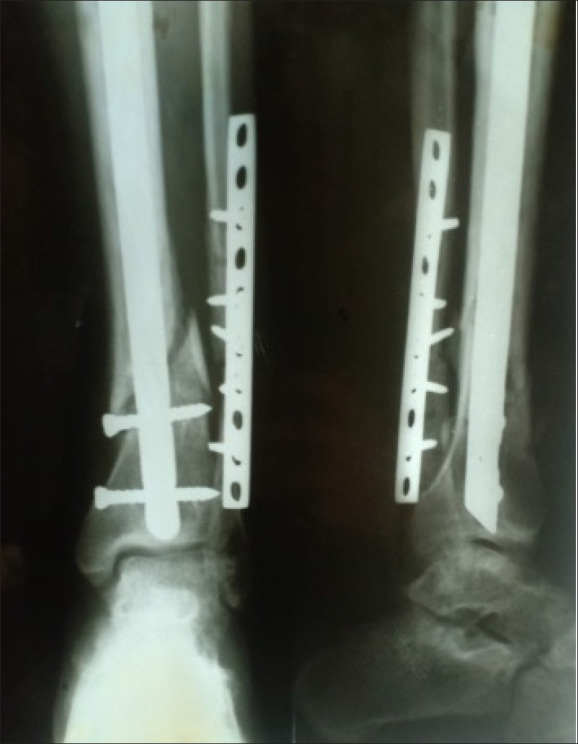

{"title":"Radiographic and functional results of Ilizarov fixation in the management of nonunion of tibia and femur fractures: a retrospective case series.","authors":"Mohamed A A Ibrahim, Khalid M Alhomayani, Usama Gaber, Hashem A Bukhary, Samir A Nematallah, Mostafa M Elgahel","doi":"10.5144/0256-4947.2024.146","DOIUrl":null,"url":null,"abstract":"<p><strong>Background: </strong>Femoral and tibial fractures may result in delayed union and nonunion, posing significant challenges in orthopedic practice. The Ilizarov technique has emerged as a promising solution for managing these complex cases.</p><p><strong>Objectives: </strong>Evaluate the radiographic and functional results of Ilizarov fixation in the treatment of nonunion of tibia and femur fractures.</p><p><strong>Design: </strong>Retrospective.</p><p><strong>Settings: </strong>Hospitals affiliated with a university hospital.</p><p><strong>Patients and methods: </strong>Patient demographics, fracture characteristics, and treatment details were analyzed for the period from October 2015 to September 2022 in patients who were treated for nonunion of the tibia and femur using the Ilizarov fixator. Clinical and radiological assessments were performed using the Association for the Study and Application of Methods of Ilizarov (ASAMI) criteria. The study focused on assessing the average duration for union and frame removal, bone results, successful union rates, and functional results using the ASAMI criteria, obtaining data from the existing medical records, spanning various medical facilities treating nonunion fractures.</p><p><strong>Sample size: </strong>126 patients.</p><p><strong>Results: </strong>The average duration for union and frame removal was 8 months, with excellent bone results observed in 60.32% of cases. Out of 126 patients, 118 achieved successful union, while there were 2 failure cases necessitating amputation (1.52%). Functional results revealed excellent outcomes in 39.68% of cases. Complications included pin tract infections, ankle and knee stiffness, and limb shortening. External fixation duration and infection eradication were consistent with previous research, emphasizing the technique's effectiveness.</p><p><strong>Conclusions: </strong>The Ilizarov technique proved highly effective in managing nonunion tibia and femur fractures, offering favorable outcomes in terms of union, infection control, pain relief, and functional recovery. While excellent bone outcomes do not guarantee optimal function, this method remains a reliable approach for complex cases.</p><p><strong>Limitations: </strong>Potential biases inherent in retrospective analyses and the need for further randomized controlled trials to comprehensively compare treatment modalities.</p>","PeriodicalId":93875,"journal":{"name":"Annals of Saudi medicine","volume":"44 3","pages":"146-152"},"PeriodicalIF":0.0000,"publicationDate":"2024-05-01","publicationTypes":"Journal Article","fieldsOfStudy":null,"isOpenAccess":false,"openAccessPdf":"https://www.ncbi.nlm.nih.gov/pmc/articles/PMC11268481/pdf/","citationCount":"0","resultStr":null,"platform":"Semanticscholar","paperid":null,"PeriodicalName":"Annals of Saudi medicine","FirstCategoryId":"1085","ListUrlMain":"https://doi.org/10.5144/0256-4947.2024.146","RegionNum":0,"RegionCategory":null,"ArticlePicture":[],"TitleCN":null,"AbstractTextCN":null,"PMCID":null,"EPubDate":"2024/6/6 0:00:00","PubModel":"Epub","JCR":"","JCRName":"","Score":null,"Total":0}

Patients and methods: Patient demographics, fracture characteristics, and treatment details were analyzed for the period from October 2015 to September 2022 in patients who were treated for nonunion of the tibia and femur using the Ilizarov fixator. Clinical and radiological assessments were performed using the Association for the Study and Application of Methods of Ilizarov (ASAMI) criteria. The study focused on assessing the average duration for union and frame removal, bone results, successful union rates, and functional results using the ASAMI criteria, obtaining data from the existing medical records, spanning various medical facilities treating nonunion fractures.

Results: The average duration for union and frame removal was 8 months, with excellent bone results observed in 60.32% of cases. Out of 126 patients, 118 achieved successful union, while there were 2 failure cases necessitating amputation (1.52%). Functional results revealed excellent outcomes in 39.68% of cases. Complications included pin tract infections, ankle and knee stiffness, and limb shortening. External fixation duration and infection eradication were consistent with previous research, emphasizing the technique's effectiveness.

Conclusions: The Ilizarov technique proved highly effective in managing nonunion tibia and femur fractures, offering favorable outcomes in terms of union, infection control, pain relief, and functional recovery. While excellent bone outcomes do not guarantee optimal function, this method remains a reliable approach for complex cases.